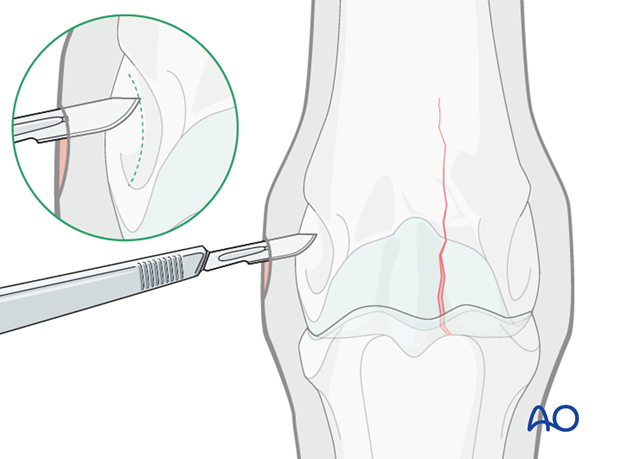

An incision is made with a #10 scalpel blade parallel to the fibers of the collateral ligament directly down to the bone surface. The epicondylar fossa is recognizable with the tip of the scalpel as it follows its contour.

In most cases, 4.5 mm cortex screws are used.